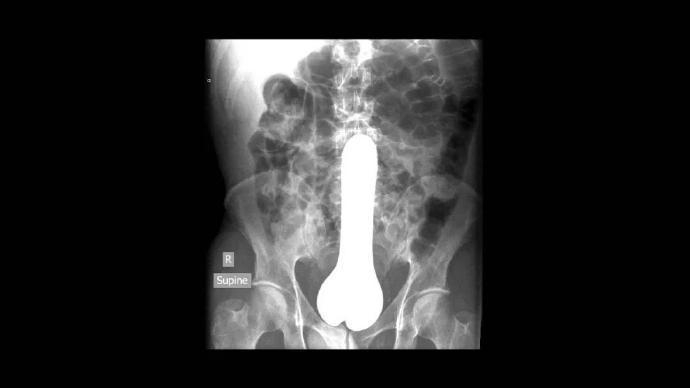

据统计,在急诊室中,男性“失物招领”的情况是女性的40倍,大部分失物是在肠道中被发现的,而且花样繁多……